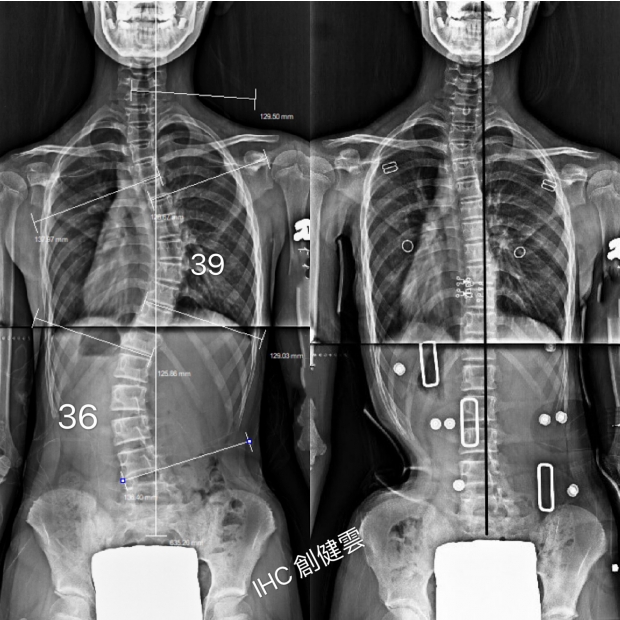

15歲脊椎側彎男孩

胸彎40度